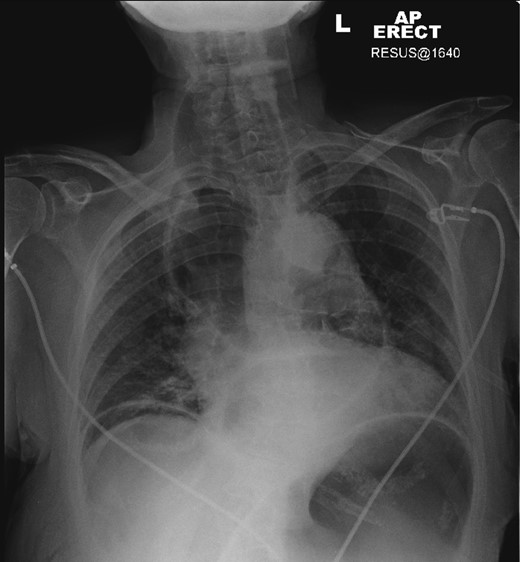

A plain chest radiograph was taken demonstrating a massively dilated air and fluid-filled oesophagus, with no visible intraparenchymal lung abnormality. A 16-French gauge nasogastric tube was immediately placed into the oesophagus with aspiration of air, fluid and food debris. This resulted in almost immediate relief of the patient's respiratory distress, and she clinically improved.

After decompression of the oesophagus, a computed tomography (CT) scan of the chest confirmed the diagnosis of megaoesophagus causing tracheal compression. The patient, now stabilized, was referred for oesophago-gastro-duodenoscopy (OGD) with a view to Botulinum toxin treatment for underlying achalasia (Figures 1–3).